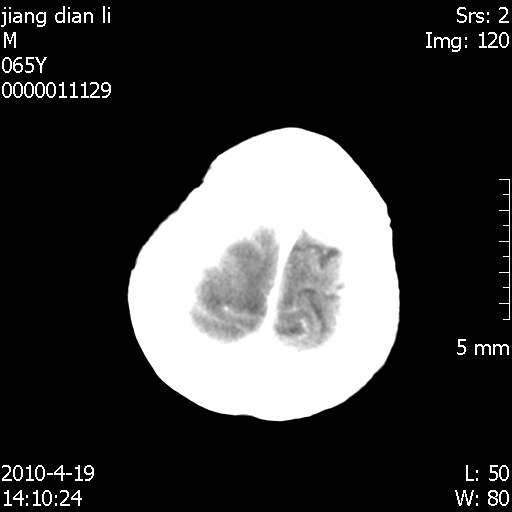

老年男性,突发左下肢无力1天,其余有价值的检查都没有。平扫ct值大约60hu,增强后ct值没什么改变,请大家讨论一下这个病例是什么?说明诊断理由。

左小脑、右大脑顶叶多发圆形高密度病灶,其周环状低密度影。考虑多发脑出血。隔期观察。

今天上班后发现病人前天复查(4月18日发病,19日初诊,22日复查),三个病灶均明显增大,边缘仍旧清楚,水肿加重,右侧脑室基本闭塞。

基于这样的表现,不知大家有什么看法?(临床其他检查我还没有追踪)

我想:如果是肿瘤出血的话,一般不会导致体积明显改变,水肿又进一步加重;如果是出血灶,那么现在应该正好是水肿加重的时候,还是比较符合,但是为什么边缘又是这样的特点?